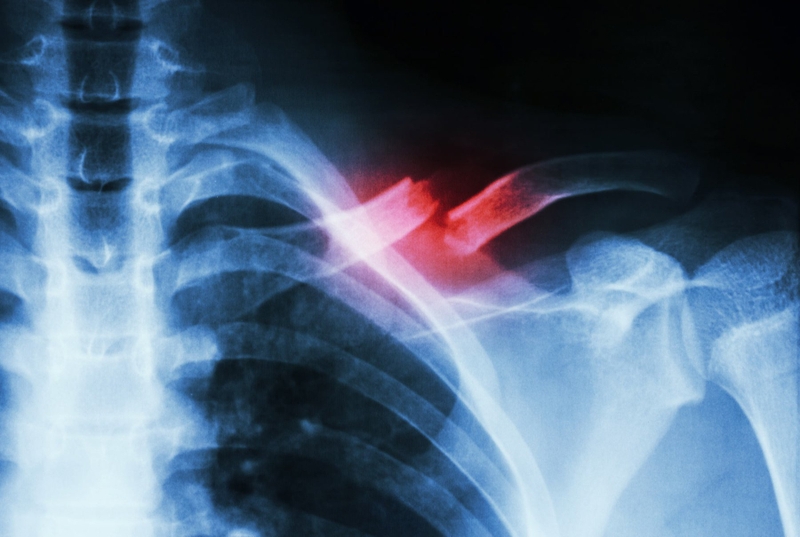

Trong quá trình phục hồi sau một chấn thương xương, việc theo dõi và nhận biết liệu xương đã lành hay chưa là một vấn đề quan trọng. Vậy làm sao biết xương đang lành? Hãy cùng nhà thuốc Long Châu tìm hiểu qua bài viết dưới đây nhé!

Đối với những người bị gãy xương hay đang điều trị các bệnh liên quan đến hệ xương thì việc làm sao nhận biết xương đang lành là cực kì quan trọng. Sự hiểu biết về việc xác định xương đã lành hay chưa sẽ giúp đảm bảo xương được phục hồi toàn diện, đúng cách và tránh các biến chứng có thể xảy ra.

Gãy xương có thể gây ảnh hưởng khác nhau đến cơ thể tùy thuộc vào mức độ và tình trạng của gãy xương. Khi xảy ra gãy xương do tai nạn hoặc tác động từ nguồn lực bên ngoài, nó khác với các bệnh lý về cơ xương khớp. Do đó, có thể gây ra các tác động từ nhẹ đến nghiêm trọng đối với người bệnh. Gãy xương dẫn đến sự thay đổi trong cấu trúc xương và mô mềm xung quanh. Các cục máu đông được hình thành và làm tắc các mạch máu nhỏ xung quanh vết thương. Hơn nữa, cấu trúc mạch máu của tủy xương cũng bị ảnh hưởng và tái cấu trúc. Các tác động tức thì của gãy xương có thể bao gồm: